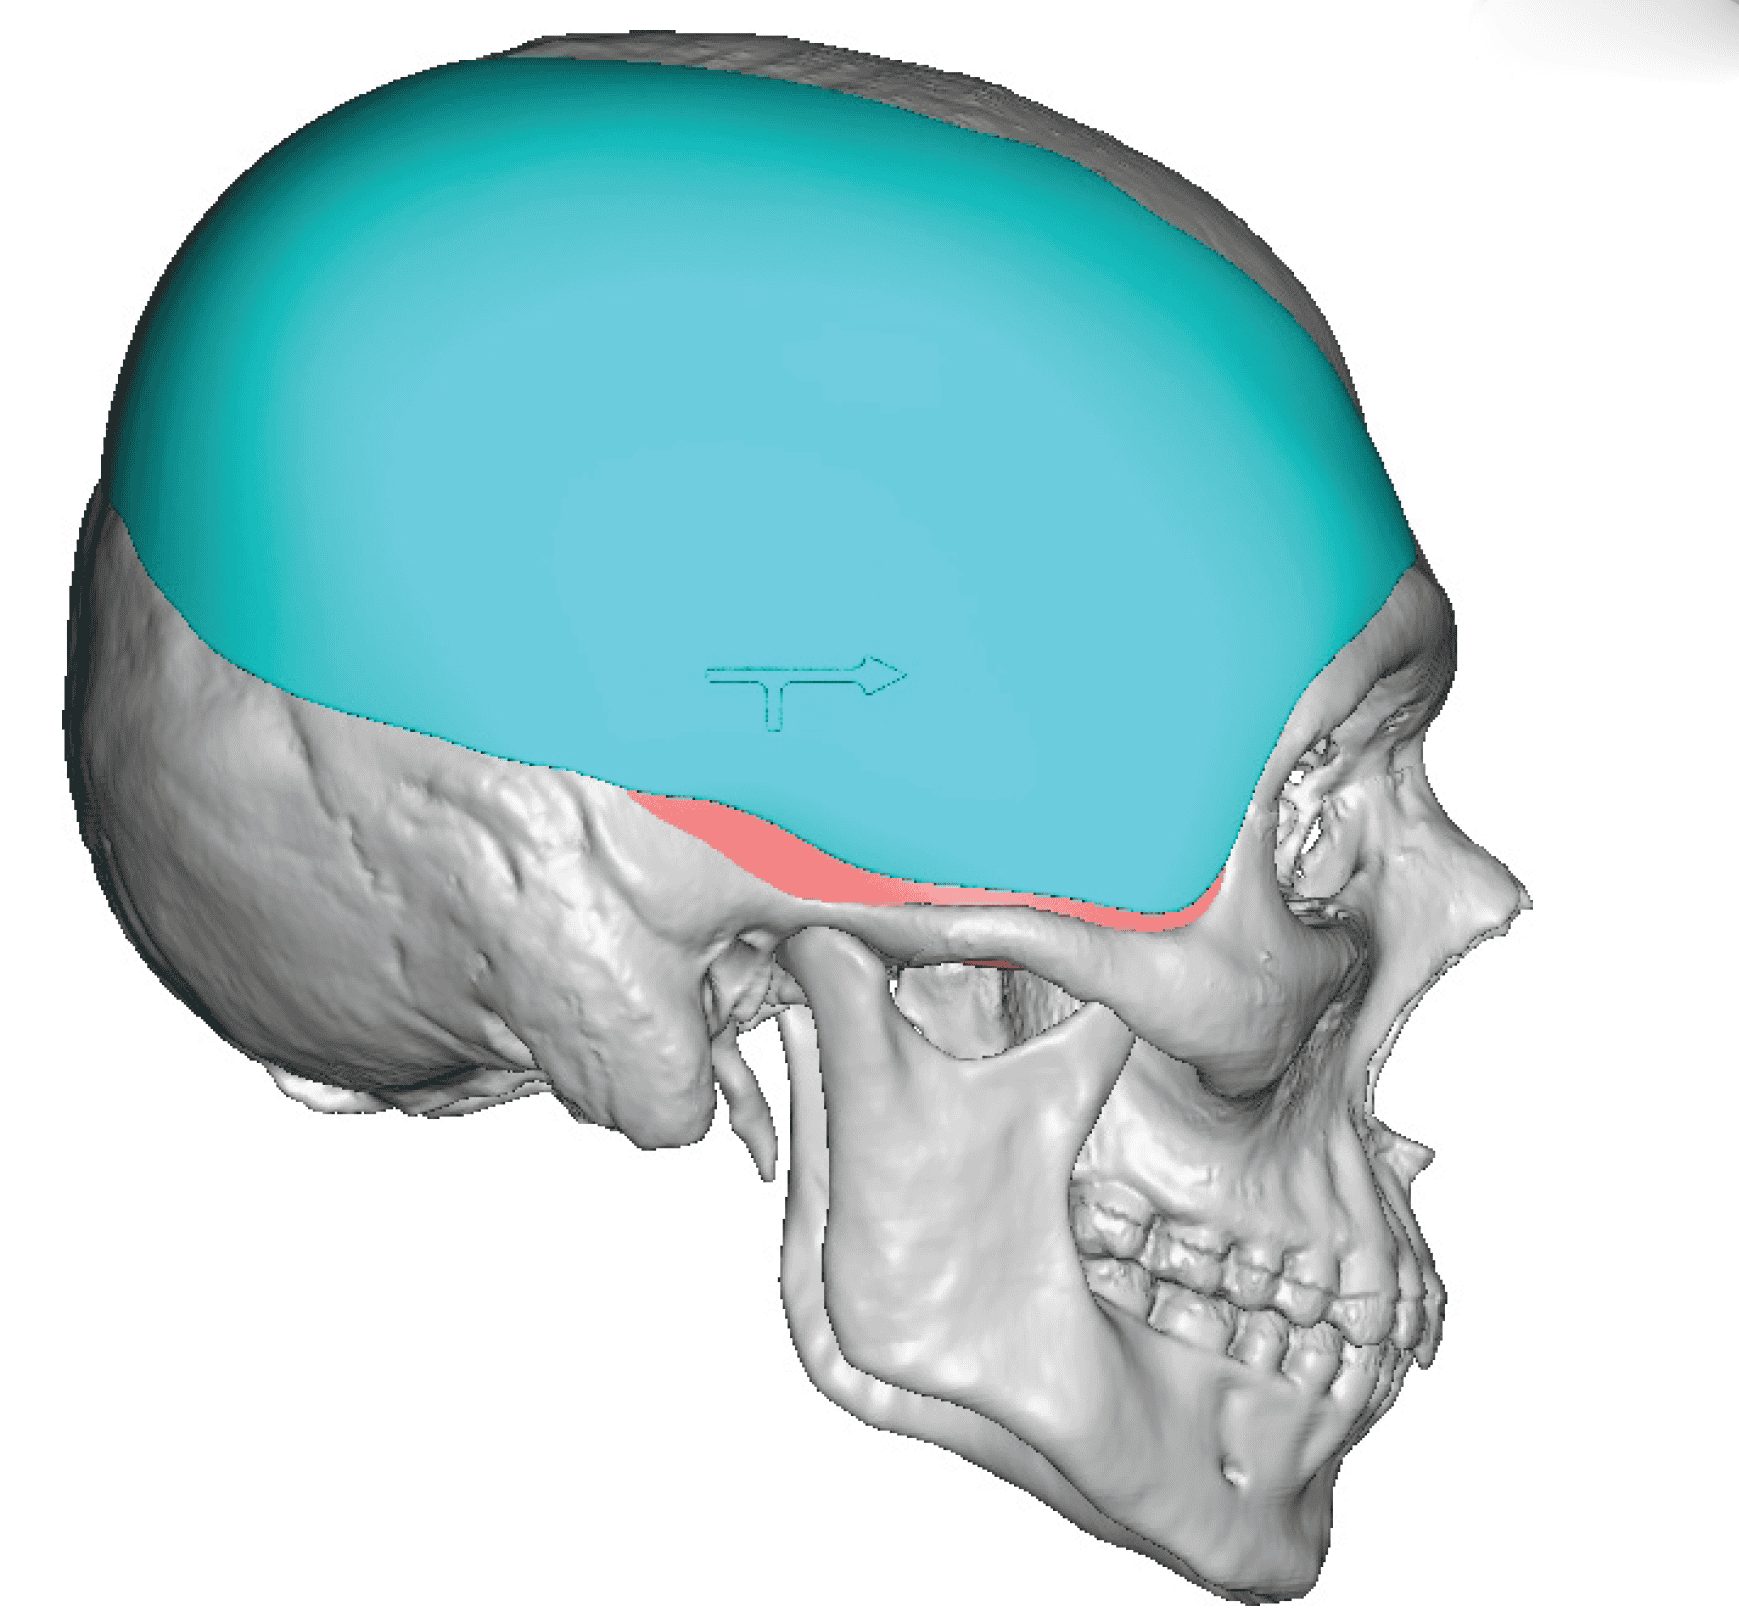

Desire for major head reshaping with a taler and wider head shape.

Placement of large two piece custom skull implant through a sagittal scalp incision.

Desire for major head reshaping with a taler and wider head shape.

Placement of large two piece custom skull implant through a sagittal scalp incision.